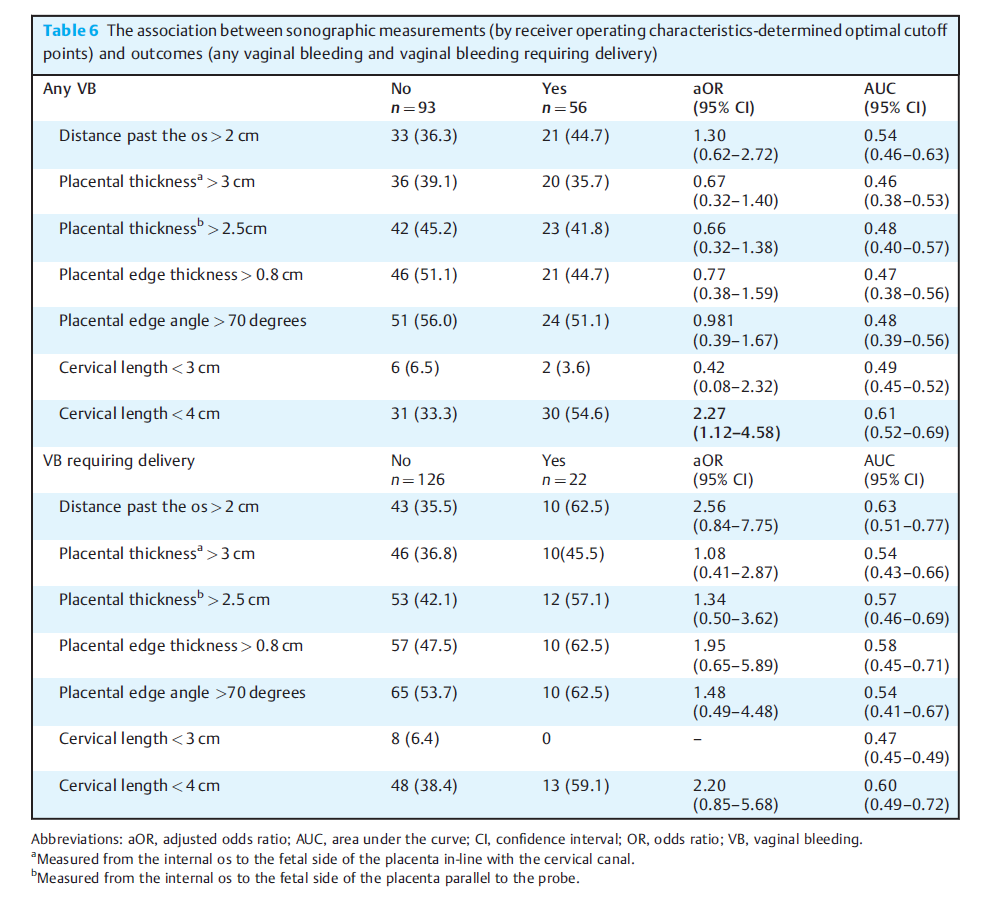

需要分娩的女性与没有分娩的女性相比,DPO增加(2.6 cm IQR[1.7-3.3]比1.5 cm [1.1-2.4], p < 0.01)。校正混杂因素后,只有CL < 4 cm与VB风险增加独立相关(校正优势比:2.27,95%可信区间[1.12-4.58],p < 0.01),见下表。